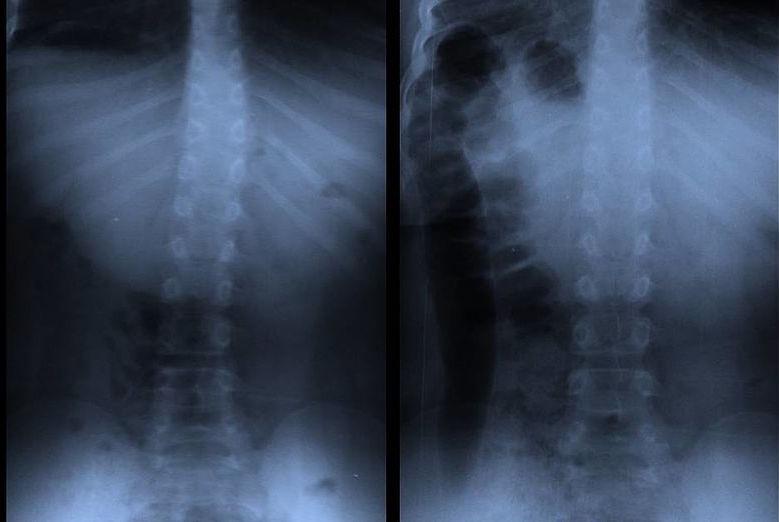

Skoliose Behandlung

Skoliose